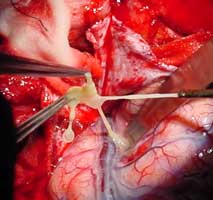

(2)毛黴菌病:為條件致病感染,可分為全身型與鼻眼腦型。全身型多發生於免疫功能低下時,鼻眼腦型則多見於糖尿病酸中毒病人。毛黴菌侵犯血管,發生血管炎導致血管閉塞,造成乾性壞死,因而藥物不易達到病灶處。毛黴菌病死亡率極高,必須早期診斷,配合外科切除病灶,積極抗黴菌藥物治療,才有存活希望。藥物用二性黴素B或氟康唑,或聯合用藥。